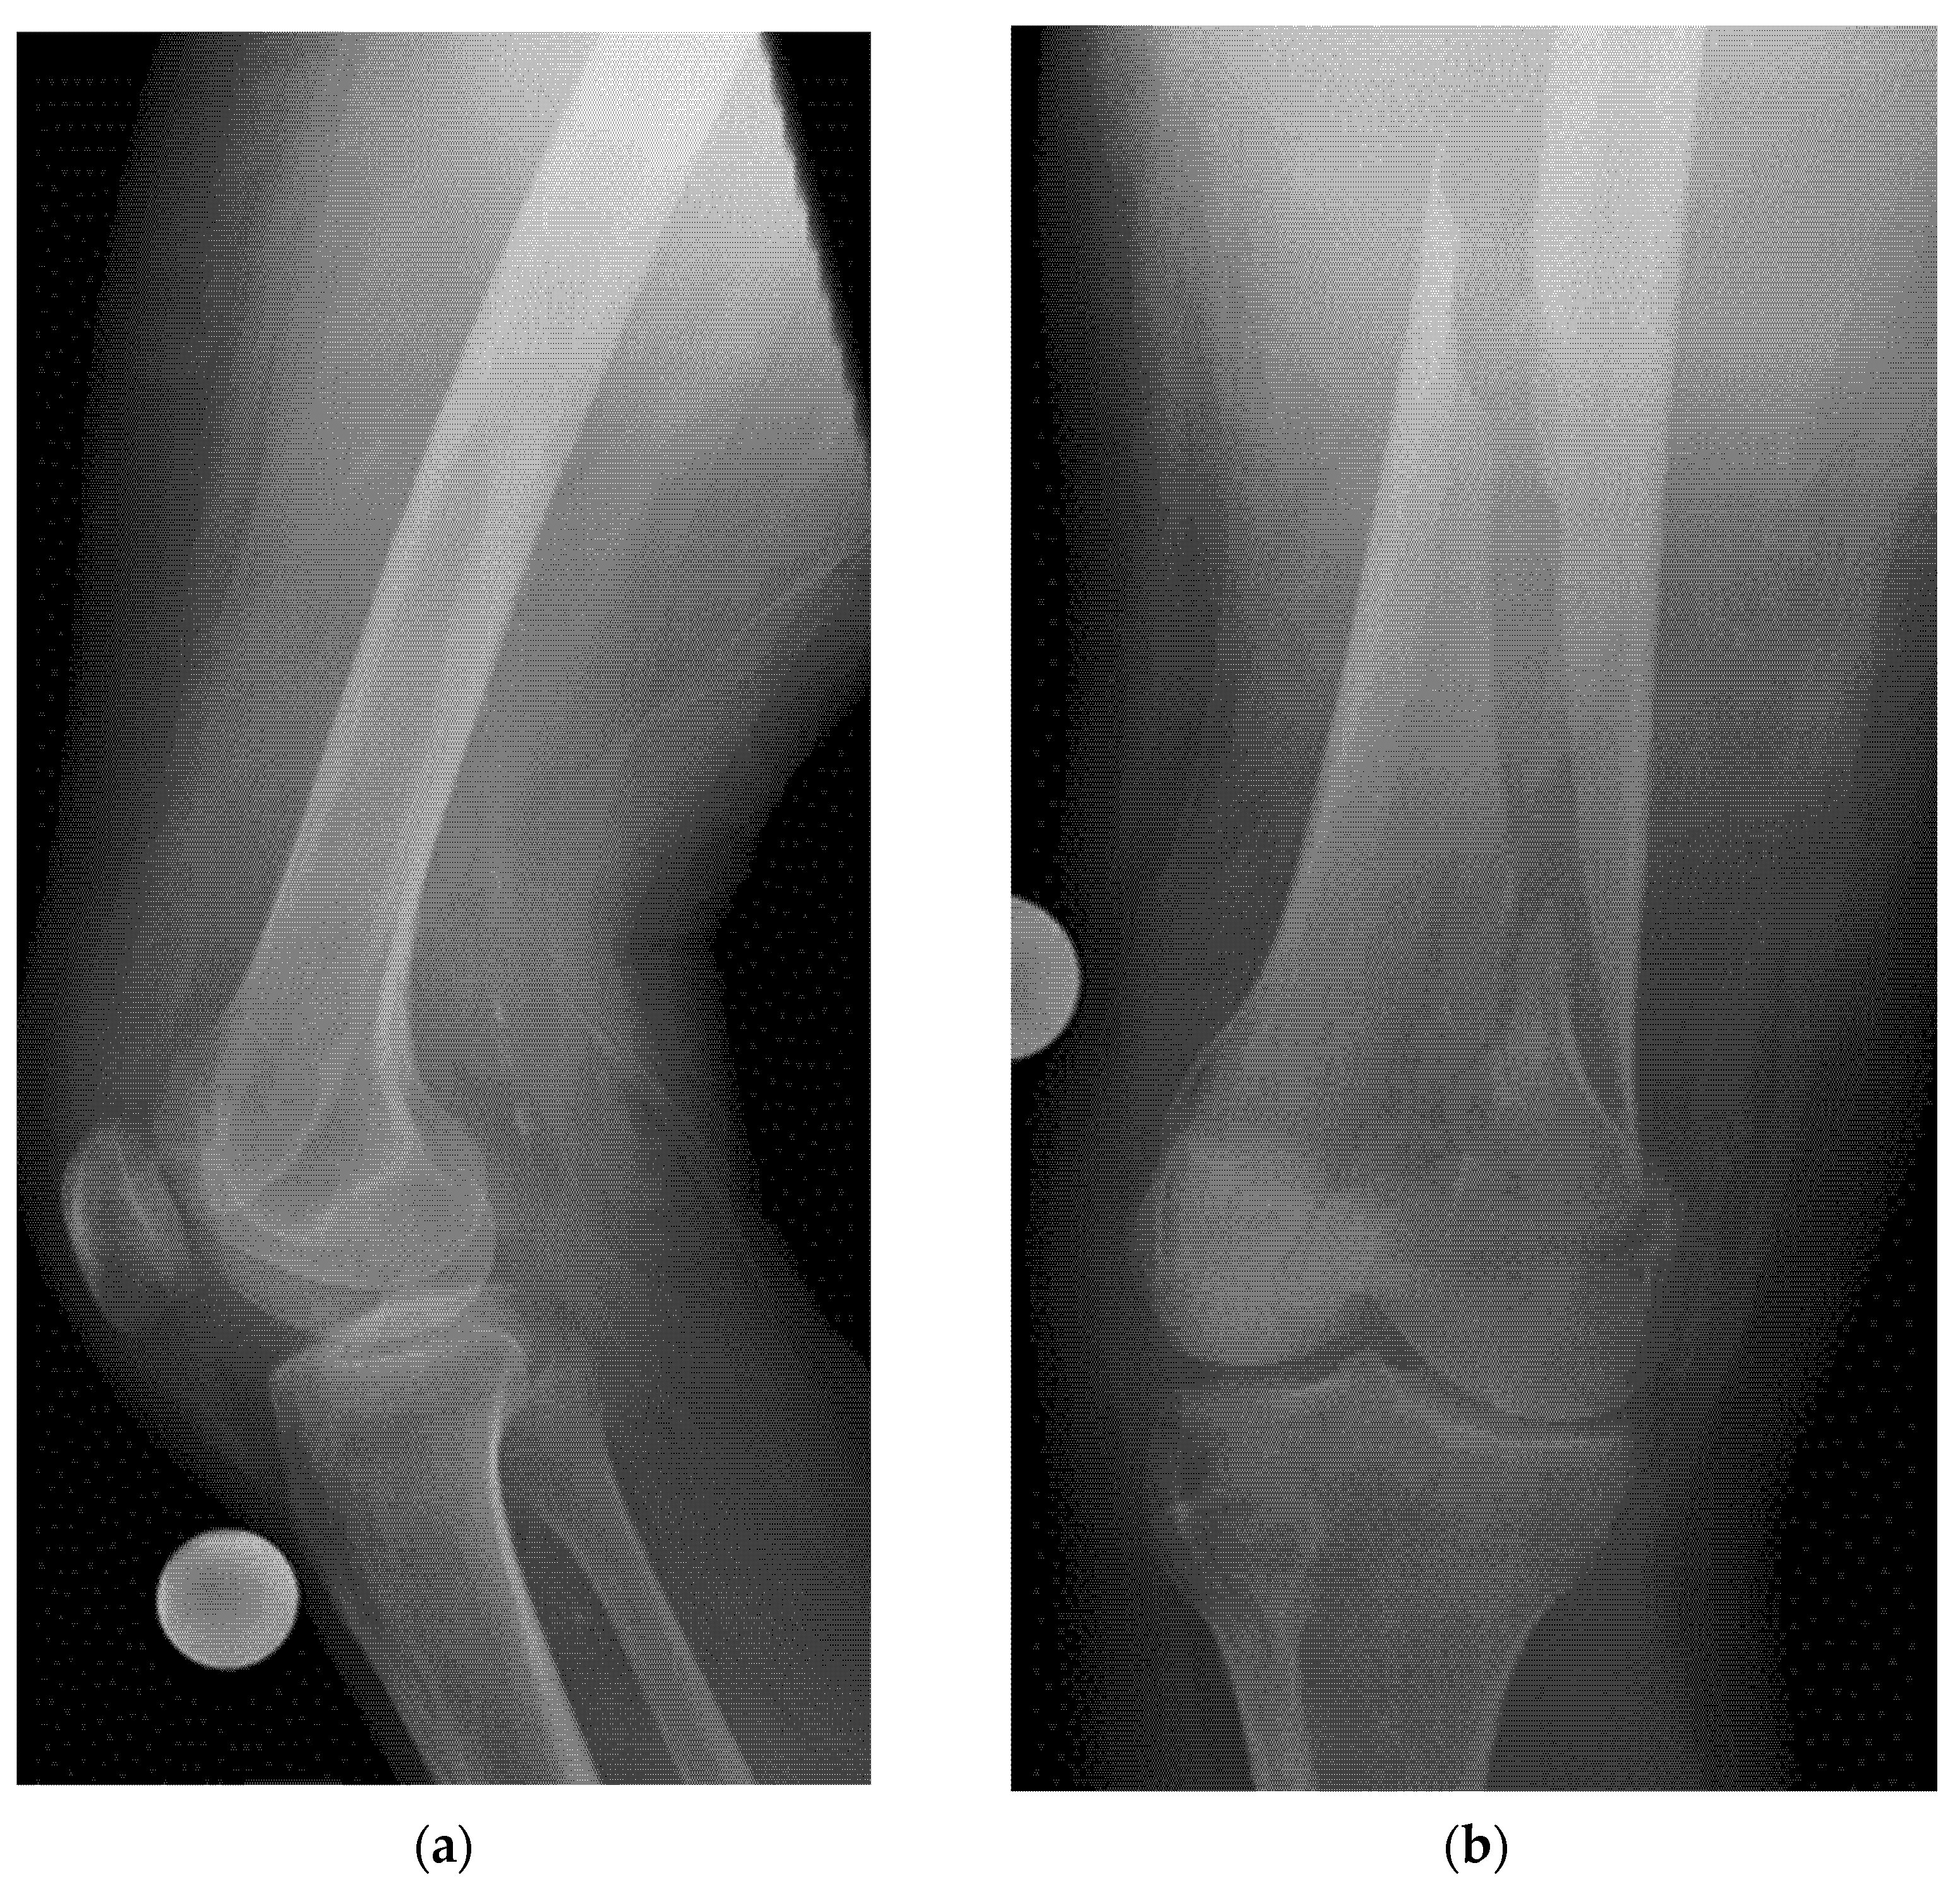

- Example: Hemorrhagic Shock Due to Distal Femur Fracture—Rapid Diagnosis via Ultrasound

- Joint effusion and liphemarthrosis: fluid accumulation within a joint, sometimes containing fat droplets, which often indicates an intra-articular fracture.